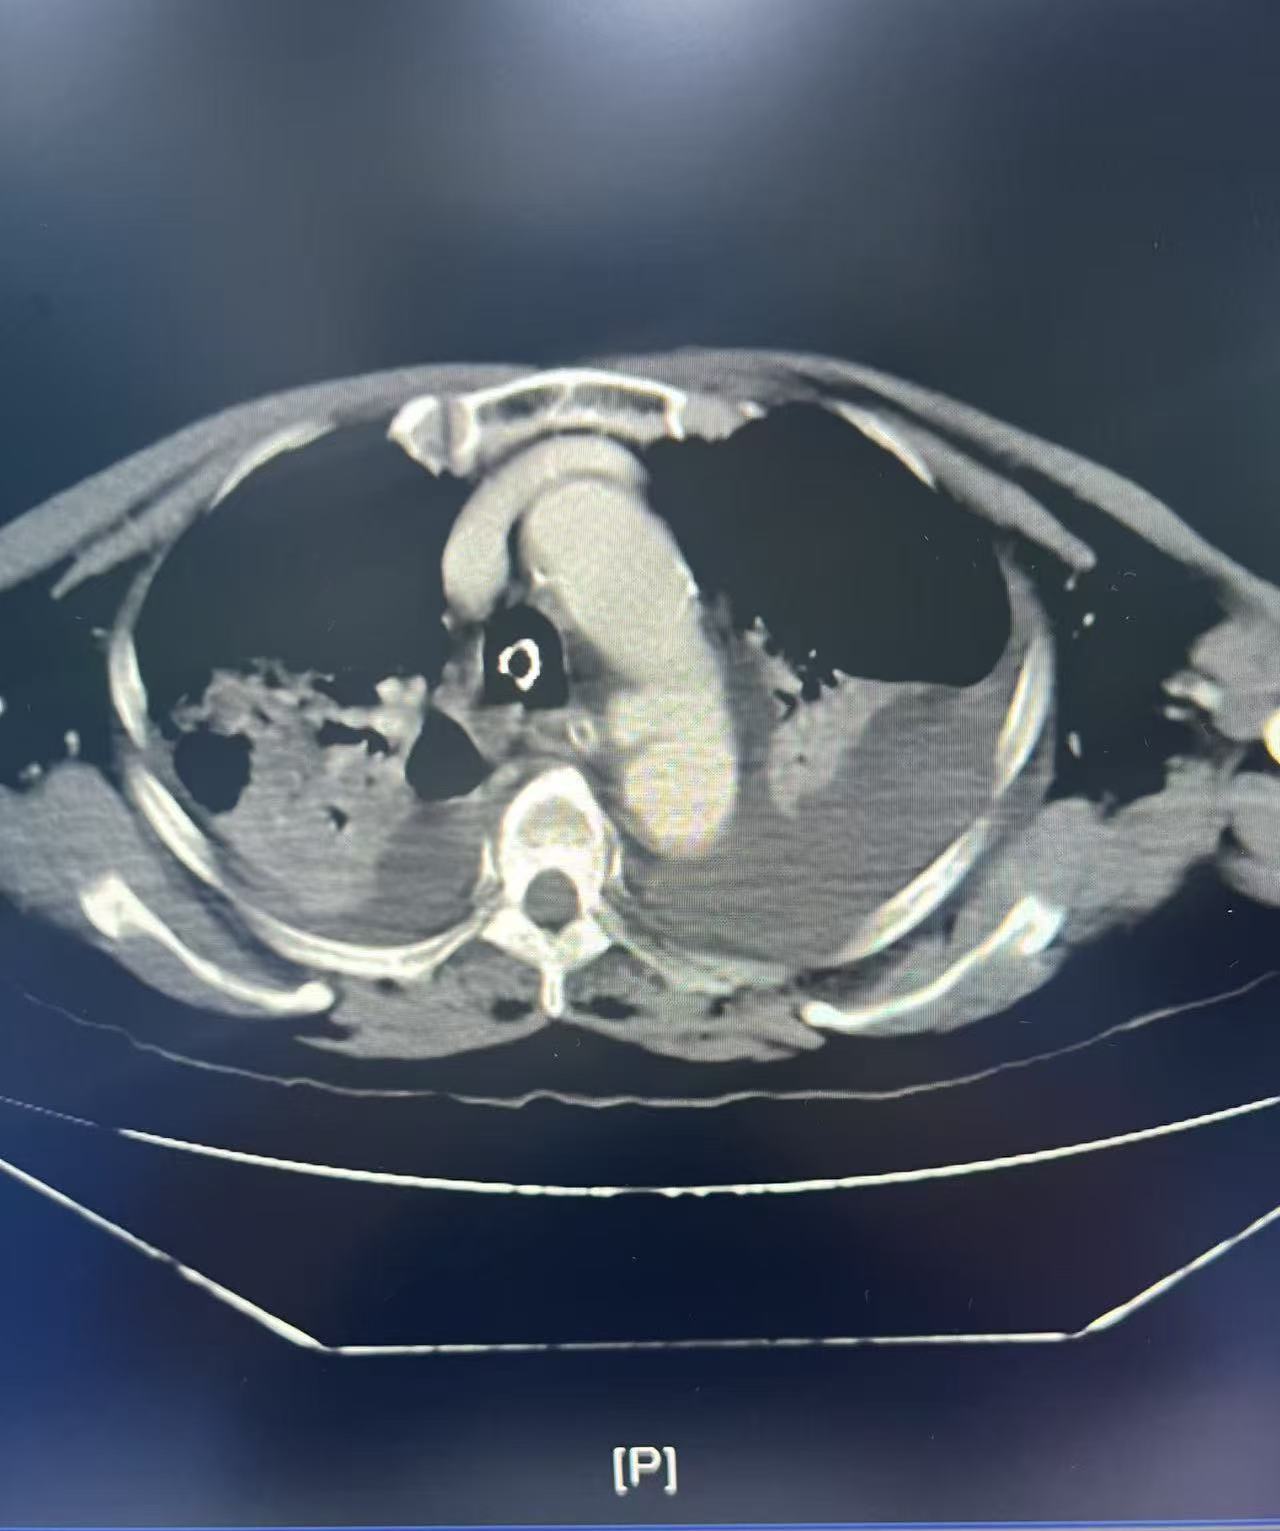

术前

患者女,66岁,三楼坠落导致全身多发伤,双侧多发肋骨骨折伴血气胸、骨盆粉碎性骨折伴左髋关节脱位、胸腰椎多发骨折等。尤其胸主动脉因外伤性穿孔形成假性动脉瘤,犹如体内的“不定时炸弹”,就是胸主动脉外伤性破裂穿孔出血后暂时被周围组织包裹,一旦周围血肿吸收或血压增高、血管壁进一步撕裂随时可能引发大出血,传统开胸手术修补胸主动脉创伤大、风险高,对患者身体状况要求极高。